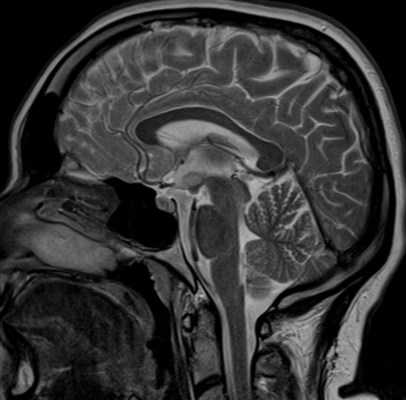

- МРТ головного мозга. На снимках МРТ визуализируется объемное образование однородной структуры с четкими контурами, которое не накапливает контрастное вещество, не имеет признаков инвазивного роста. При исследовании в режиме Т1 очаг является гипоинтенсивным, а в Т2-режиме — переменным гиперинтенсивным.

ГГ I типа растут из мамиллярной области и способны вызывать смещение и деформацию мамиллярных тел. При этом свод смещается кпереди и латерально, наблюдается расширение III желудочка. Исследования показывают, что в 97 % случаев при магнитно-резонансной томографии выявляют интрагипоталамическое распространение ГГ, которая оттесняет кпереди переднюю комиссуру свода и серое вещество гипоталамуса и располагается между сводом мозга, мамиллярными телами и мамиллярно-таламическим трактом. Гамартомы не прогрессируют, но по мере развития головного мозга увеличиваются в размерах .Интенсивность сигнала при стандартной магнитно- резонансной томографии определяется строением ГГ.

Поскольку по структуре она напоминает кору, на Т1-взвешенных изображениях (ВИ) ГГ выглядит изоинтенсивной, на Т2-ВИ - изо- или гиперинтенсивной. Степень повышения интенсивности сигнала на Т2-ВИ напрямую зависит от количества глиальных клеток в ГГ. Увеличение количества глиальных клеток также коррелирует с размером ГГ, что подтверждается при патоморфологическом исследовании. По периферии ГГ, в отличие от глиом, имеется гипоинтенсивный ободок, представляющий собой слой миелиновых волокон и особенно хорошо заметный на стандартных Т2-ВИ в режиме тонких срезов (толщиной ≤3 мм).

Структура ГГ, как правило, однородна (кисты в ГГ выявляют в 2-3 % наблюдений), а контрастное усиление в случае ГГ малоинформативно, так как они не накапливают контрастное вещество. Это сближает ГГ с другими интракраниальными опухолями, прежде всего с глиомой гипоталамуса и хиазмы, и затрудняет дифференциальный диагноз.